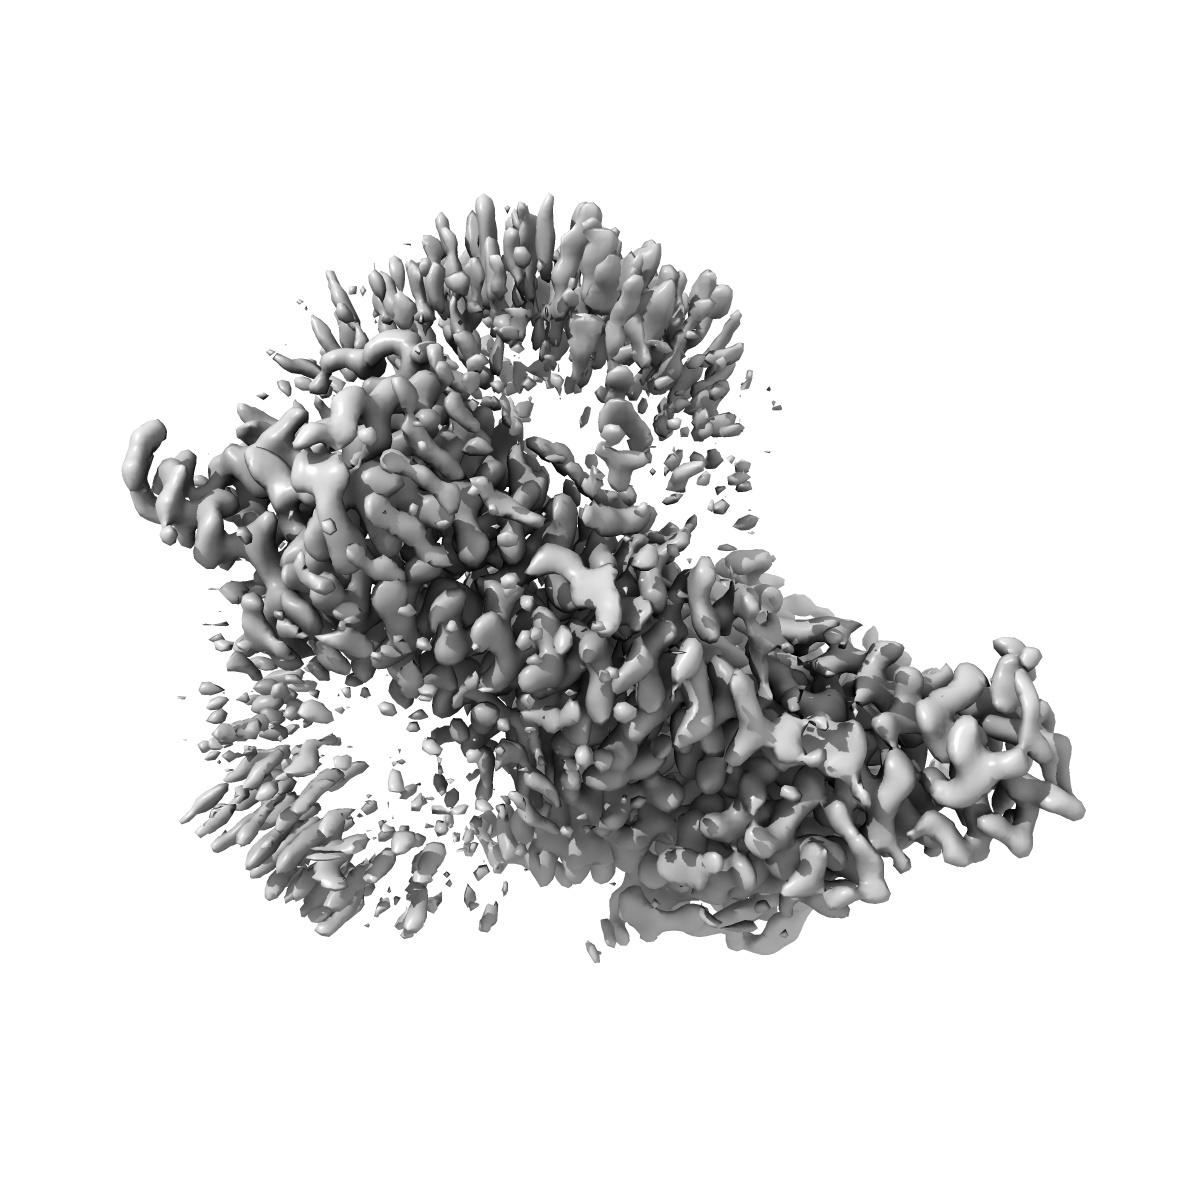

Cryo-EM structure of the human adenosine A1 receptor-Gi2-protein complex bound to its endogenous agonist and an allosteric ligand

Single-particle3.2 Å

Sample: Human adenosine A1 receptor-Gi2-protein complex bound to its endogenous agonist adenosine